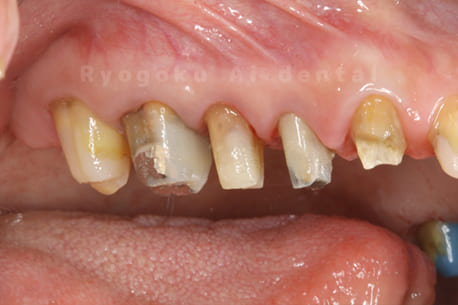

Case08

-

- 原因

- 重度カリエス

- 治療日数

- 約半年

- 治療内容

- クラウンレングスニング、根管治療、ジルコニアクラウン

- 治療費用

- 約1,200,000円

前歯が動くとのことでご来院された患者様です。虫歯が大きく保存困難な状態でしたが、ご本人様と十分話し合い、抜歯を行わず、手術をすることで歯を抜かず保存しました。

<リスク・副作用>

過度の咬合や衝撃で割れることがあります。手術後は痛み、腫れ、痺れ、青あざなどの副作用が生じます。痛みは痛み止めを処方しますが、腫れ、青あざは1週間程度生じる場合があります。また、部位によっては神経の走行が複雑で、痺れが残り、長期的にお薬を処方する場合があります。